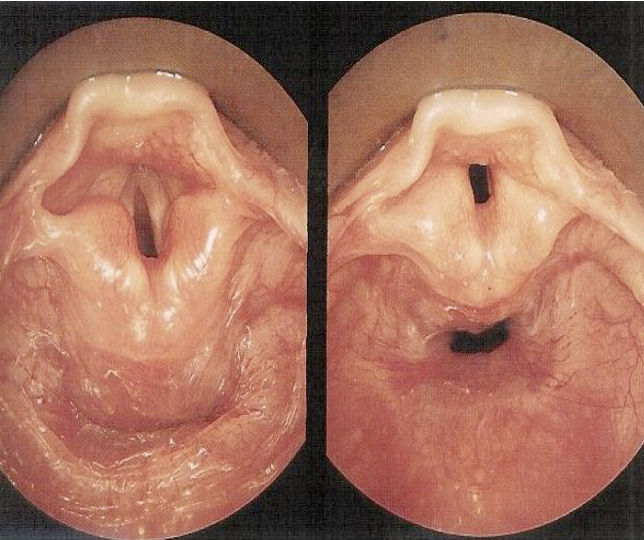

Respiration

- Vocal cord in abduction position

Vocal Cord Vibration

- Vocal folds vibrate rapidly in sequence of vibratory cycles with a speed of about: